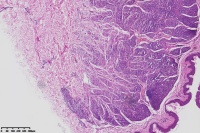

背部包块,皮内痣?

性别

女

年龄

41岁

背部包块

图3

考虑符合:皮内痣

皮内痣

皮肤皮内痣,切缘未净